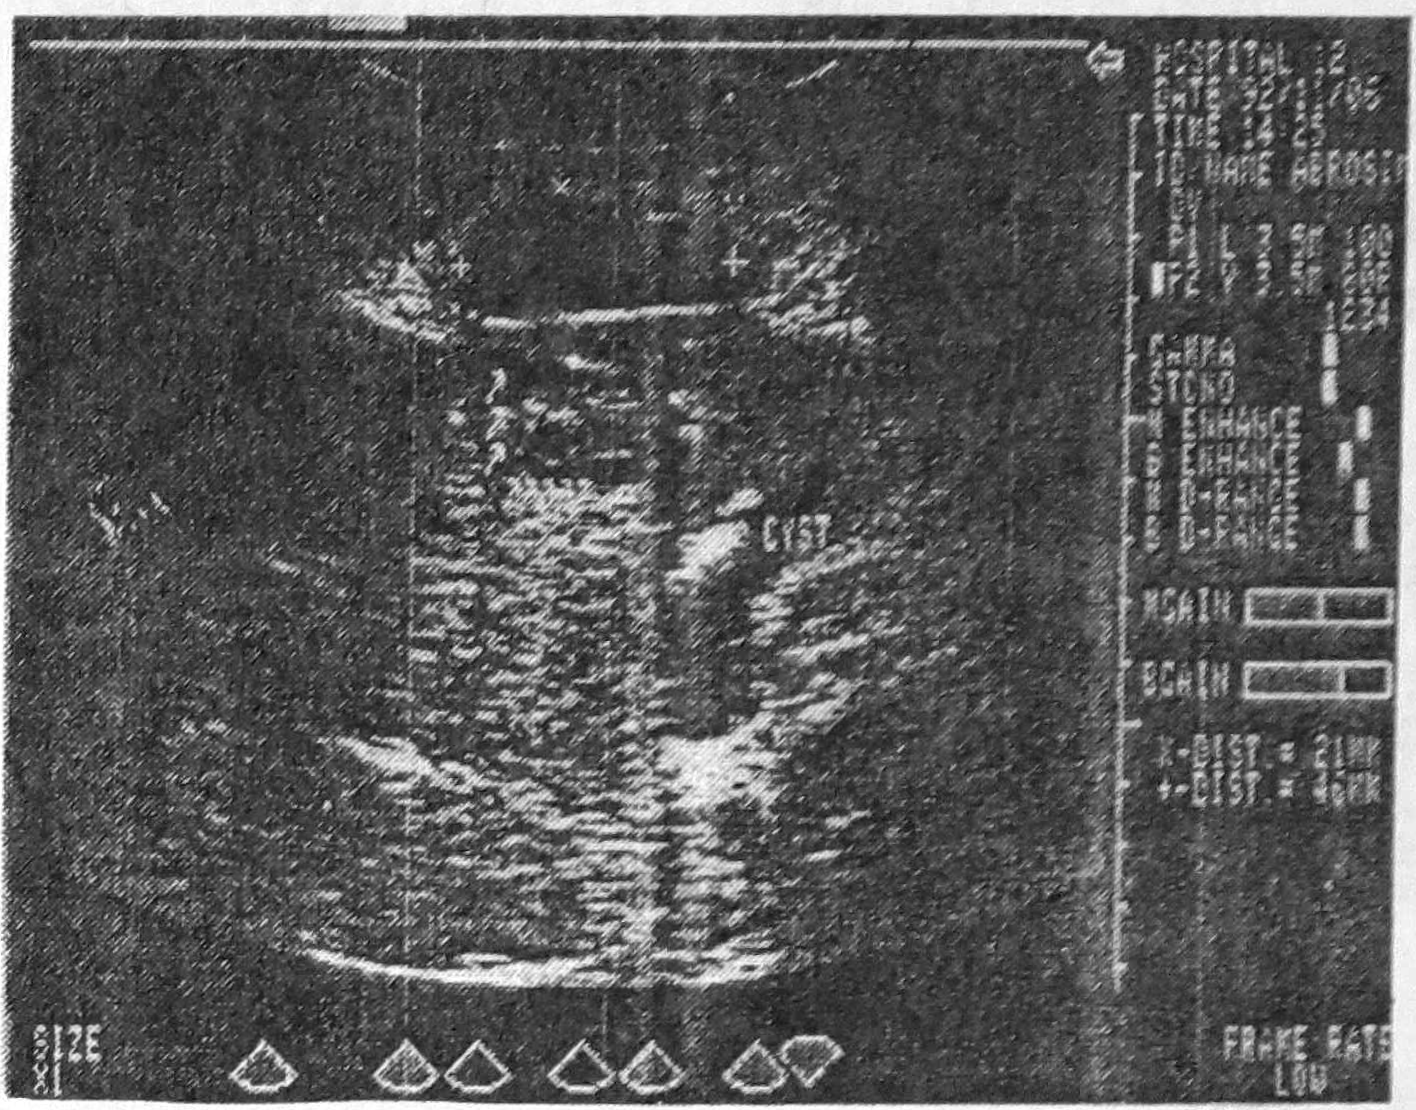

Ультразвуковое исследование: в V сегменте печени рядом с желчным пузырем определяется гипоэхогенное образование (46 х 46 мм) с нечеткими контурами и неоднородной плотностью, а между париетальной брюшиной и печенью в этой же зоне — эхонегативное образование (46 х 21 мм) с ровными контурами и гомогенным содержимым. Желчный пузырь содержит небольшое количество осадка (рис. 1).

Рис. 1. Эхограмма печени больного А. Видна полость каверны, окруженная плотной тканью.